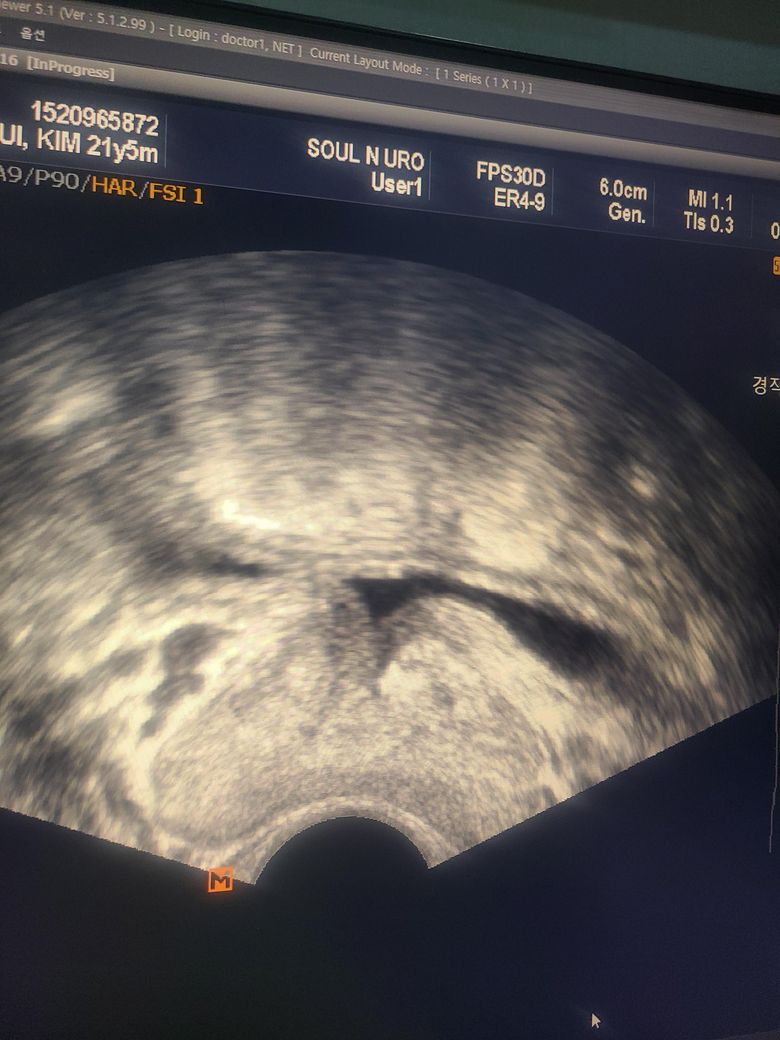

발기부전이 왔는데 증상이 오줌 발이 약해지고, 오줌이 시원찮게 나옴 (소변을 보다가, 마지막엔 뚝 뚝 끊겨서), 샤워 중 소변을 두번 봄. 등의 증상이 있어 전립선 초음파를 했는데 전립선염 진단을 받았습니다. 근데 전립선염이 심한 편인가요? 저 정도로 발기부전이 올 수가 있나요?

• 1번 째 사진

전립선염이 심한 정도는 증상의 강도와 지속 기간, 염증 상태에 따라 다릅니다. 딱히 초음파 자체로 파악하긴 어려워요 (그리고 이건 영상의학과 전문의에게 의뢰하셔야 정확하게 해석 가능합니다). 오줌발이 약해지고 시원하게 나오지 않으며, 마지막에 끊기는 증상은 전립선 부위의 염증이나 부종으로 인해 요도가 압박받아 발생할 가능성이 큽니다. 또한 샤워 중에도 소변을 자주 보게 되는 것은 전립선이 자극을 받아 방광이 예민해졌을 가능성이 있구요